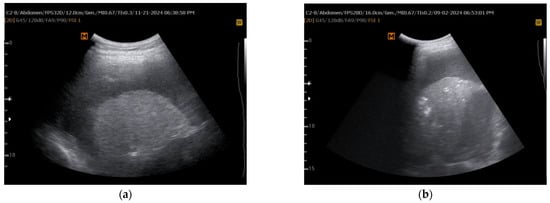

| lung/liver echogenicity (LLE) ratio | Compares grayscale pixel density of lung and liver via ImageJ software | Predicting lung re-expansion after pleural drainage | LLE > 1.6 predicts NEL with AUC = 0.77 | Simple, reproducible, quantitative | Limited validation, small study population, dependent on image quality | Lacks direct validation against; potential role as adjunct to manometry | Requires software (ImageJ) and proper grayscale calibration, moderately operator-dependent | Larger, multicenter studies, AI-based echogenicity analysis, validation in different effusion types |